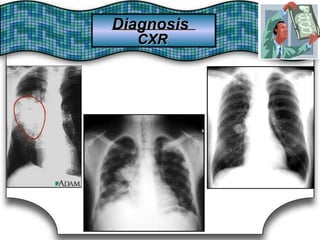

Chest X Ray (CXR)X Ray (CXR)Chest

Chest RadiographRadiographChest Suggestive DiagnosisSuggestive Diagnosis

Cardiomegaly, increasedincreasedCardiomegaly,

pulmonary vascular distributiondistributionpulmonary vascular

Chronic heartheart failure,failure, mitralmitral valve stenosisvalve stenosisChronic

Cavitary lesionsCavitary lesions Lung abscess, TB,TB, necrotizing carcinomanecrotizing carcinomaLung abscess,

Diffuse alveolar infiltratesinfiltratesDiffuse alveolar Chronic heartheart failure,failure, pulmonary edema,pulmonary edema, aspirationaspirationChronic

Hilar adenopathy oradenopathy or massmassHilar Carcinoma, metastaticmetastatic disease,disease, infectioninfectionCarcinoma,

HyperinflationHyperinflation COPDCOPD

Lobar oror segmentalsegmental infiltratesinfiltratesLobar Pneumonia, thromboembolism, obstructing carcinomathromboembolism, obstructing carcinomaPneumonia,

Mass lesion,lesion, nodules,nodules, granulomasgranulomasMass

Carcinoma,

granulomatosis,

metastatic disease, Wegener's

vasculitides

Carcinoma, metastatic disease, Wegener's

septic embolism,granulomatosis, septic embolism, vasculitides

Patchy alveolar infiltratesinfiltratesPatchy alveolar

Bleeding disorders, idiopathic pulmonaryBleeding disorders, idiopathic pulmonary

hemosiderosis, Goodpasture's syndromesyndromehemosiderosis, Goodpasture's